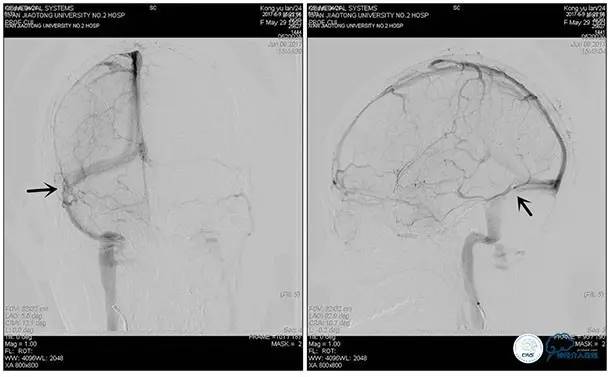

术中造影

5ml/s,总量8ml,压力100~150

术后造影

术毕远近端压力差为:0

狭窄较前有改善

术中右侧ICA造影

右侧ICA斜位及窦内造影

右侧ICA斜位

窦内造影及路图

术中测压:

远端:520mmH2O,

近端:190mmH2O。

术后右侧ICA造影

术后远、近端压力差为:0

术后右侧ICA斜位